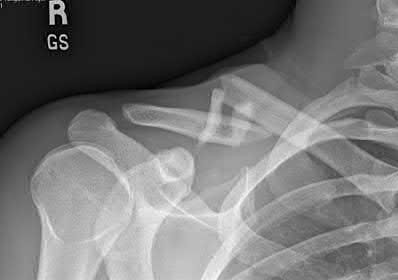

A 12-year-old obese male presents with left groin pain and an altered gait. Based on the presumed diagnosis of slipped capital femoral epiphysis (SCFE) shown in the representative radiograph, which of the following is the primary blood supply to the femoral head that is at highest risk for iatrogenic injury during percutaneous in situ pinning if the pin is placed in the posterosuperior quadrant?

The primary blood supply to the capital femoral epiphysis in children over the age of 3 is the posterosuperior retinacular vessels (lateral epiphyseal artery), which are terminal branches of the medial circumflex femoral artery (MCFA). During in situ pinning for SCFE, placement of the pin in the posterosuperior quadrant of the femoral neck/head places these extracapsular vessels at extreme risk of injury, potentially leading to avascular necrosis (AVN). Pins should ideally be placed in the center-center position to minimize this risk.